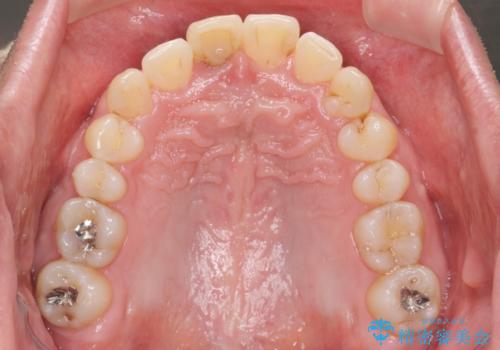

深い噛み合わせと上顎前突の状態を治すのに時間がかかりましたが、治療後は理想的で安定した咬合関係となりました。